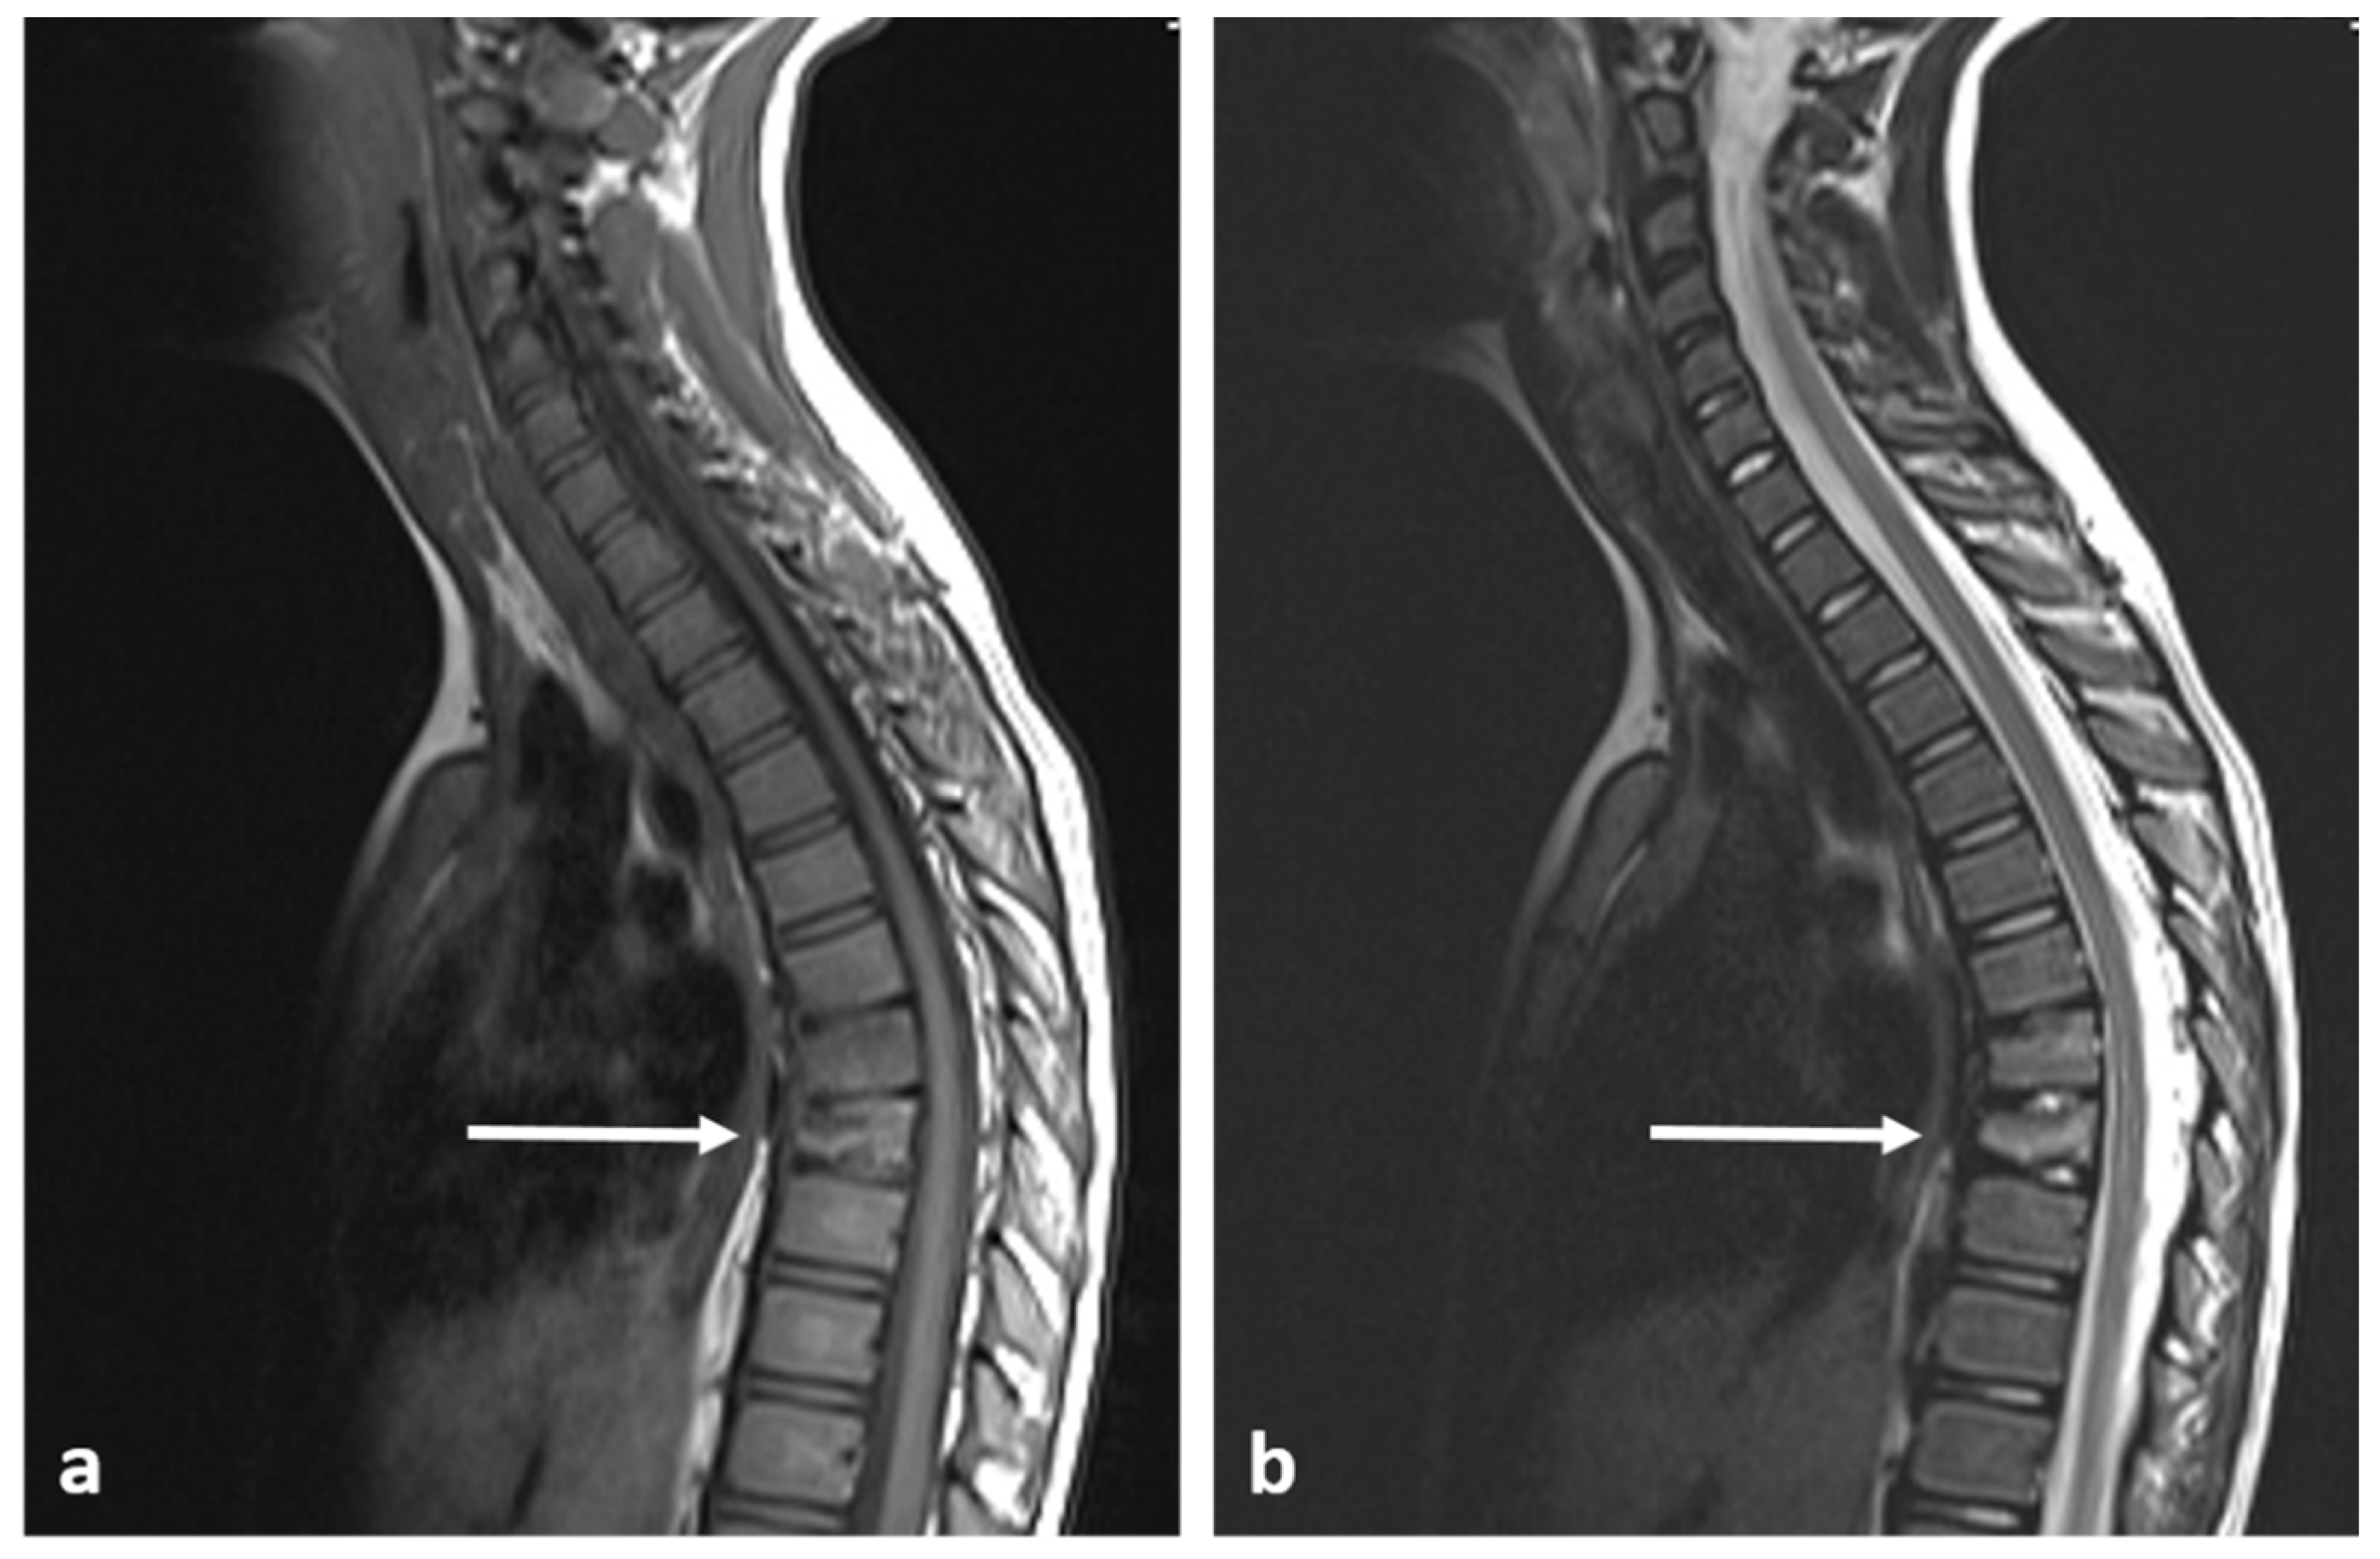

3.7. Haemangioma

- Tafti, D.; Cecava, N. Spinal Hemangioma; StatPearls Publishing: Treasure Island, FL, USA, 2022. [Google Scholar]

- Cloran, F.J.; Pukenas, B.A.; Loevner, L.A.; Aquino, C.; Schuster, J.; Mohan, S. Aggressive spinal haemangiomas: Imaging correlates to clinical presentation with analysis of treatment algorithm and clinical outcomes. Br. J. Radiol. 2015, 88, 20140771. [Google Scholar] [CrossRef]

| Haemangioma | Honey comb appearance. ‘Corduroy’ and ‘polka dot’ signs. | Usually T1 and T2 hyperintense due to fat content. Signal drop out >20% on out of phase chemical shift imaging. |